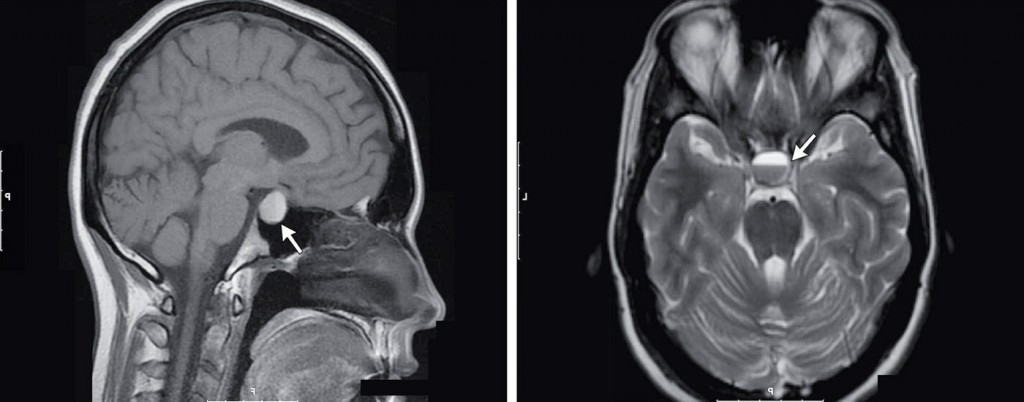

Гипоталамус — высший регулятор нейроэндокринный системы, расположенный в базальном отделе головного мозга. Он участвует в регуляции вегетативных функций организма, отвечающих за артериальное давление, проницаемость сосудов, теплорегуляцию и теплоотдачу, аппетит, обменные процессы, регуляцию сна и психической деятельности. Гипоталамус осуществляет регуляцию деятельности периферических желёз внутренней секреции через гипофиз.